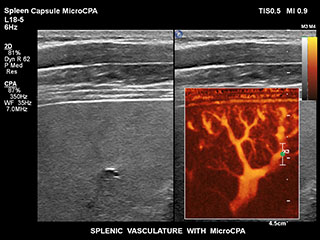

Ultrasound MicroCPA Small Vessel Visualization

MicroCPA

これまで、血流が少ない血管構造の血流情報は容易に収集できませんでした。しかし、EPIQの新しいMicroCPA機能を使用することで、低流速の微小循環を素早くかつ簡潔に描出できるようになり、臓器への灌流や小血管床の評価における診断確度が向上しました。